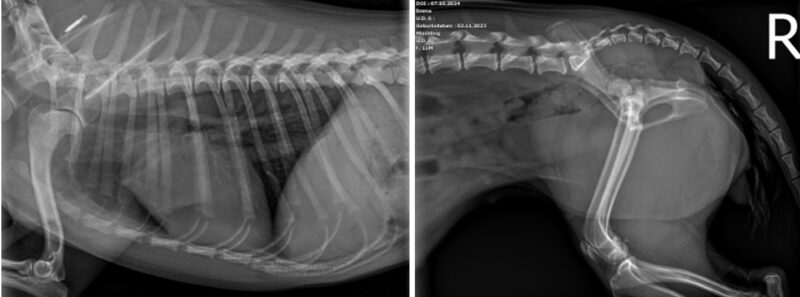

Anbei die Röntgenbilder der Hündin Gina. Gina ist eine weiblich kastrierte 1-jährige Mischlingshündin und wurde bei uns aufgrund einer Lahmheit nach Trauma vorstellig. Welche Pathologien erkennen Sie und welches weitere Vorgehen empfehlen Sie?

Vielen Dank für die Zusendung der Röntgenbilder. Uns liegt eine links laterale Aufnahme des Thorax vor. Hierbei ist die Herzschattenkontur, die Lungengefäße, das Lungenparenchym, die mediastinalen Strukturen, der Pleural Raum und die sichtbaren kranialen abdominalen Strukturen ohne besondere Befunde. Das Zwerchfell ist intakt und der abgebildete Bewegungsapparat ist normal, ohne Hinweis auf Frakturen.